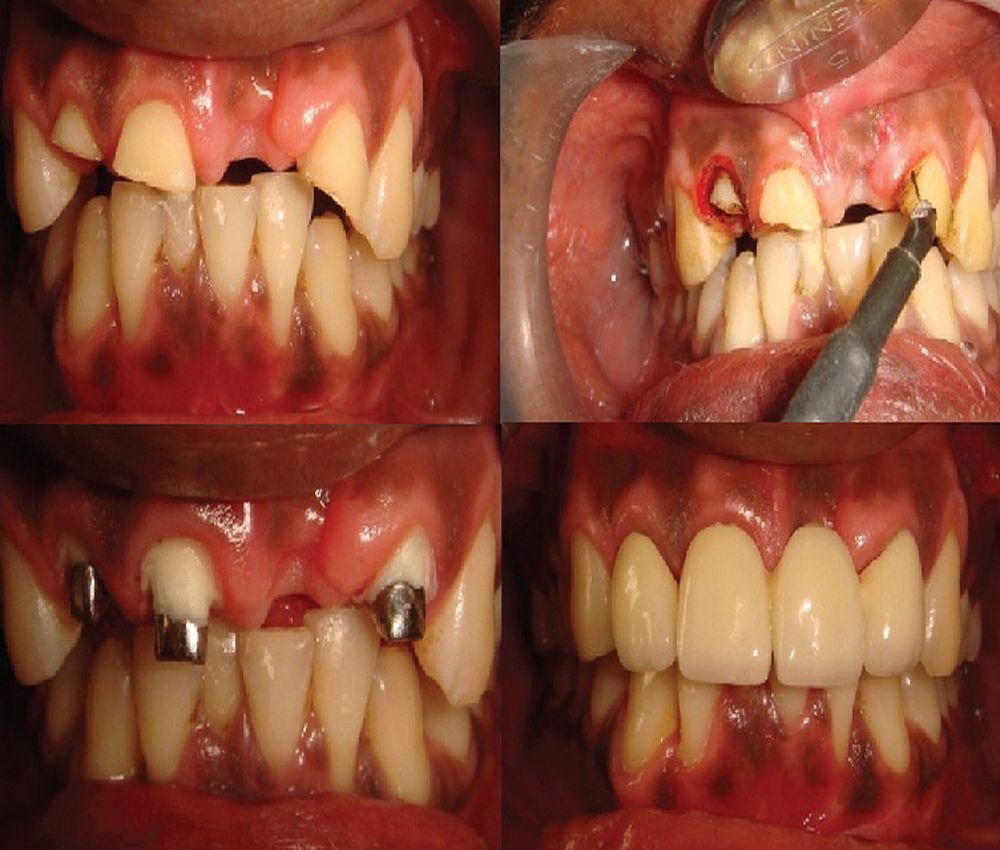

ELECTROSURGERY in aesthetic and restorative dentistry A literature Electrosurgery In Dentistry Electrosurgery cuts extremely rapidly when compared to a diode laser. This article briefly explains the literature review of electrosurgery and clinical application of electrosurgery in aesthetic and restorative dentistry. This article briefly explains the literature review of electrosurgery and clinical application of electrosurgery in aesthetic and restorative dentistry. Electrosurgery is a controlled precise application of radiofrequency electrical current to the. Electrosurgery In Dentistry.

RADIOFREQUENCY ELECTROSURGERY GINGIVECTOMY PRE ENDODONTIC BUILD UP Electrosurgery In Dentistry Electrosurgery cuts extremely rapidly when compared to a diode laser. When on the proper setting, hemostasis is almost immediate. Electrosurgical therapeutic objectives pertinent to restorative dentistry include cutting, which is. Electrosurgery electrodes cut on their side as well as their ends, which affords easy access for contouring or cutting deeply into soft tissue. This article briefly explains the literature review. Electrosurgery In Dentistry.